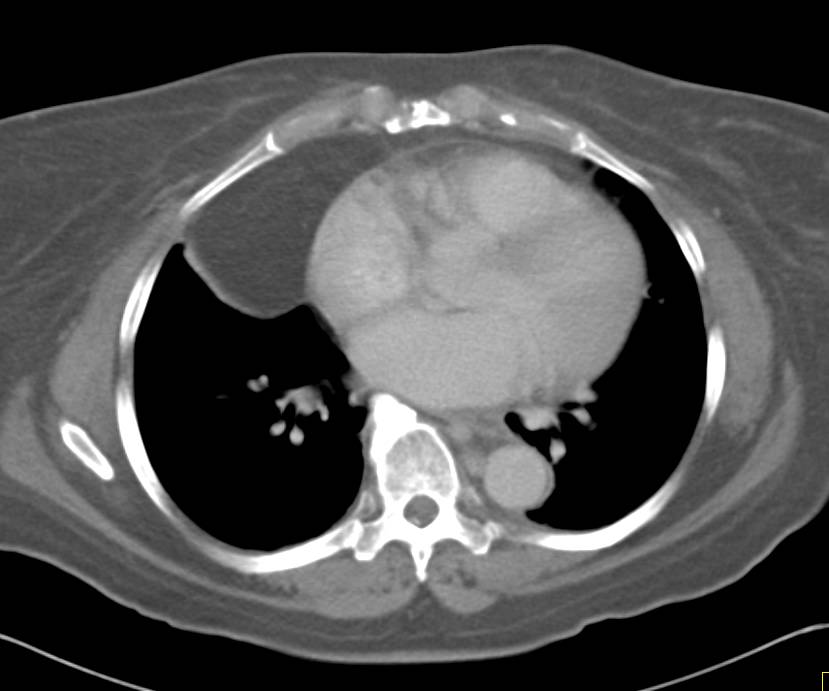

Preoperative images of computed tomography scan. Encapsulated lipoma …

Lipoma in a 42-year-old woman. Axial contrast-enhanced CT scan at the …

Pericardial Lipoma – Cardiac Case Studies – CTisus CT Scanning